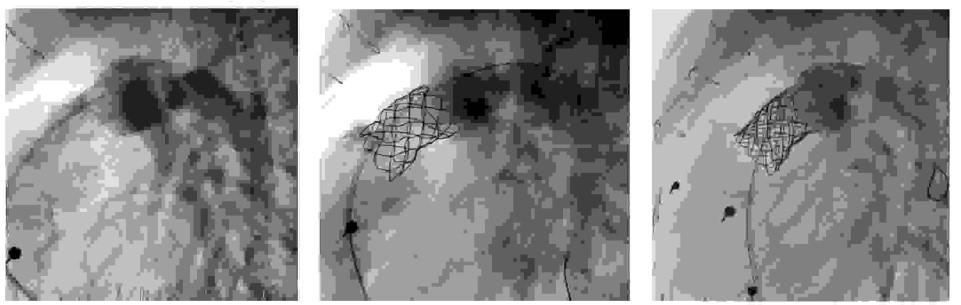

Pytanie 92

Na podstawie poniższych obrazów angiograficznych wskaż prawidłowe rozpoznanie oraz zastosowaną metodę leczenia: